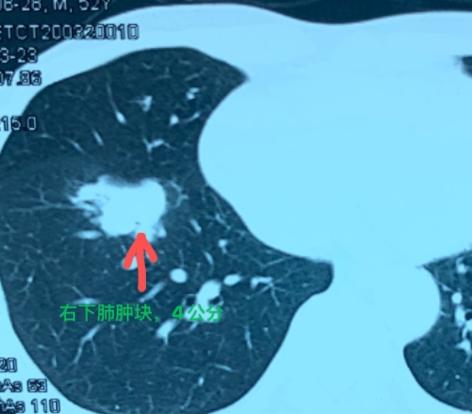

肺结节只要大于8mm,不管良恶性,都建议做手术?肺结节要不要手术,不能只看大小!虽然8mm通常是一个需要更积极关注的尺寸,但并不是“过了线”就必须开刀。 我们医生还会仔细看结节的形态,比如边缘光不光滑、有没有分叶或毛刺,也要考虑它长在肺的哪个位置,以及患者有没有咳嗽、咳血等症状,或者是不是肺癌高危人群(比如有长期吸烟史或家族史)。 如果结节超过8mm,即便是恶性,也不是所有都必须马上手术,有些磨玻璃结节还可以选择定期观察。如果是良性,或者患者存在手术禁忌症,通常就不需要手术处理。 相反,有些小于8mm的结节,如果在复查过程中发现明显增大、形态变差,也可能需要手术。所以定期随访非常重要,医生会对比最新和第一次发现时的CT的变化,再作出建议。 总之,肺结节的处理是个综合判断的过程,不是只看大小就决定。如果您发现自己有肺结节,别急着下结论,一定要找专业的胸外科看一看。[谢谢][玫瑰]